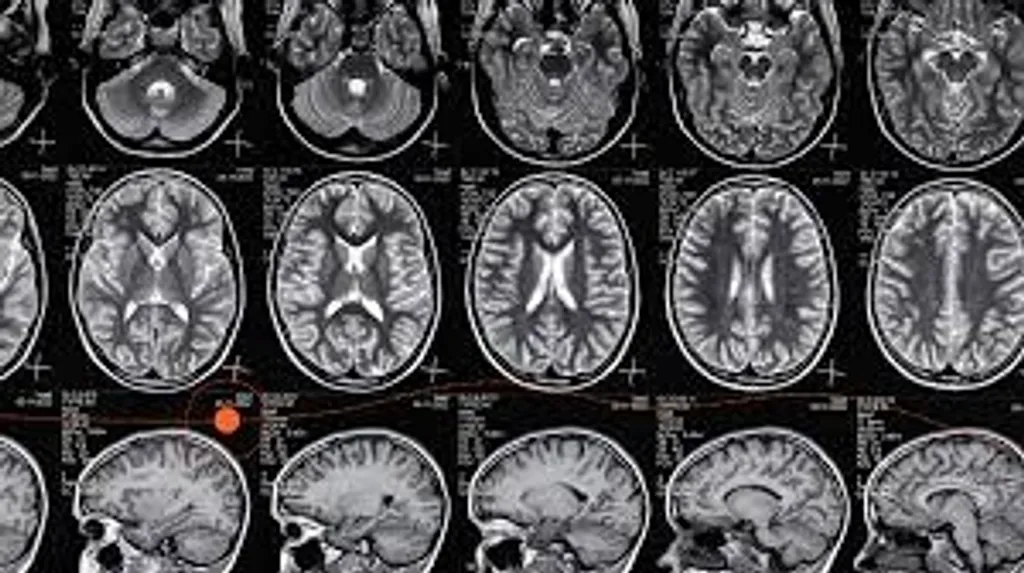

എം.ആർ.ഐ. (MRI):

മസ്തിഷ്കം, നട്ടെല്ല്, നാഡീവ്യൂഹം, മസിൽ, മജ്ജ തുടങ്ങിയവ യുടെ വിശദമായ വിലയിരുത്തൽ.

1. ന്യൂറോളജി (Neurology):

എം ആർ ഐവോള്യുമെട്രി (MRI volumetry): അൽഷിമേഴ്സ് രോഗം, പാർക്കിൻസൺ രോഗം.

ഡിഫ്യൂഷൻ ടെൻസർ ഇമേജിങ്ങ് (DTI-Diffusion Tensor Imaging): വളരെ ചെറിയ മാറ്റങ്ങൾ (Microstructural).

സി.ടി, എം.ആർ ഐ (CT / MRI) Angiography: പൊട്ടാത്ത അന്യൂറിസം (Unruptured aneurysm).

ഡിഫ്യൂഷൻ / പെർഫ്യൂഷൻ എം ആർ ഐ (Diffusion / perfusion MRI): നേരത്തെയുള്ള ഇസ്‌കീമിയ (early ischemia).